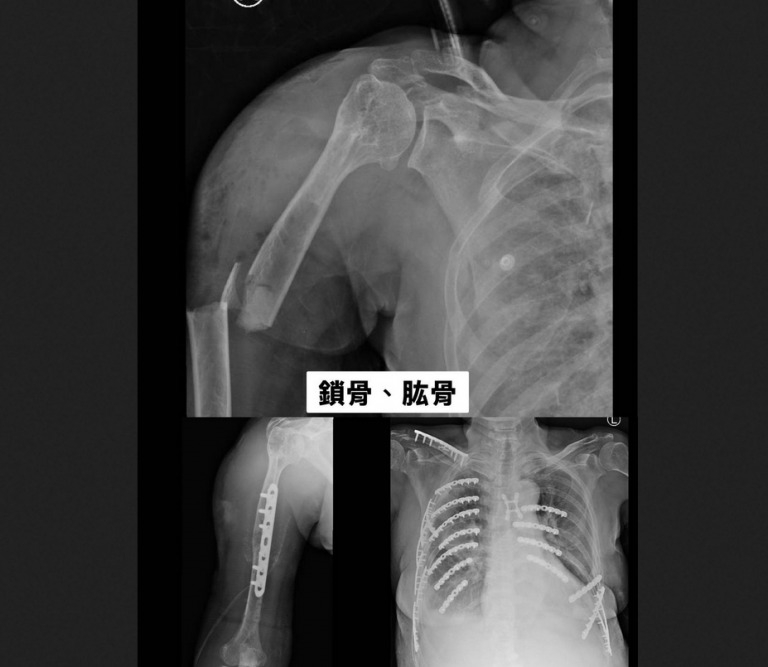

▲右上臂開放性骨折、右側血胸,右鎖骨、肱骨、橈骨、第3至5掌骨、骨盆、脛骨、腓骨,以及第6至9節胸椎、胸骨、2側多處肋骨都出現骨折。(圖╱彰化醫院提供)

黃婦被緊急送往彰化醫院急診,全身都是傷,右上臂開放性骨折、右側血胸,右鎖骨、肱骨、橈骨、第3至5掌骨、骨盆、脛骨、腓骨,以及第6至9節胸椎、胸骨、2側多處肋骨都出現骨折。由於血壓持續下降,最低僅 62/28 mmHg,因多重創傷與血胸,彰化醫院立即啟動創傷小組,並送入加護病房。

▲胸腔外科主任林聿騰指出,整個變形的胸腔透過3D胸廓重組影像定位後進行微創手術,以鈦合金骨板及骨釘進行肋骨固定,穩定整個胸腔,讓患者可以正常呼吸,再交由骨科手術。(圖╱彰化醫院提供)

林聿騰說,整個變形的胸腔透過3D胸廓重組影像定位後進行微創手術,以鈦合金骨板及骨釘進行肋骨固定,穩定整個胸腔,讓患者可以正常呼吸,再交由骨科手術。